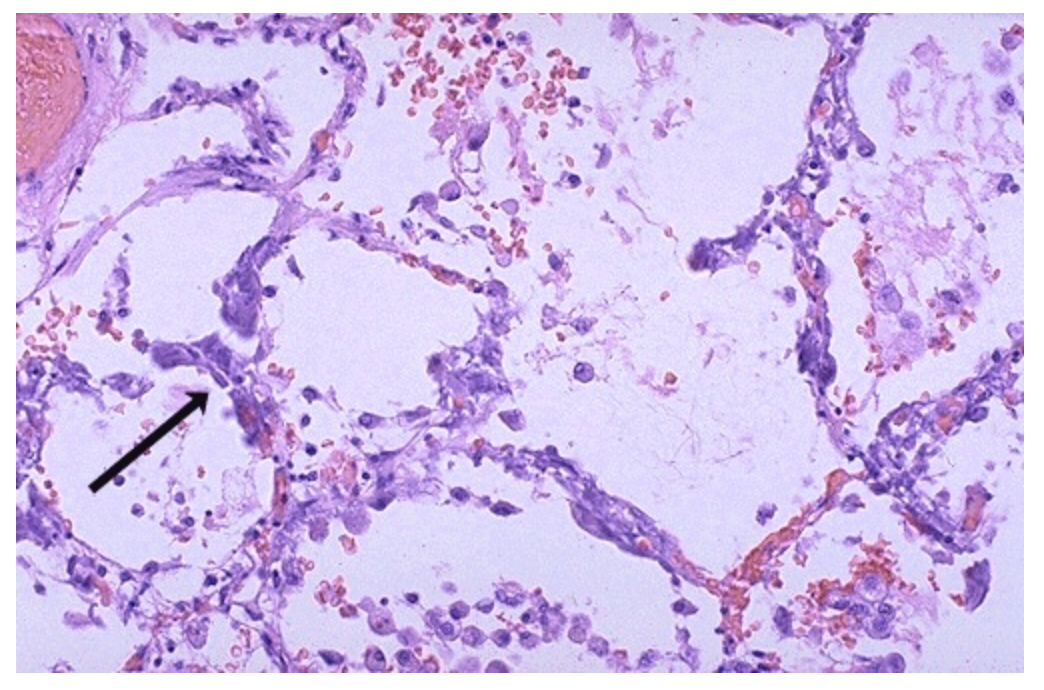

Histological section of an alveolus with macrophages. Identify what the brown coarsely granular material is. What results from this accumulation?

Hemosiderin. Breakdown of RBCs and release of iron in heme